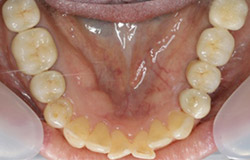

インプラントで噛み合わせの再構成を伴った症例。

治療後のメンテナンスを行わないと

周囲炎になるリスクあり。